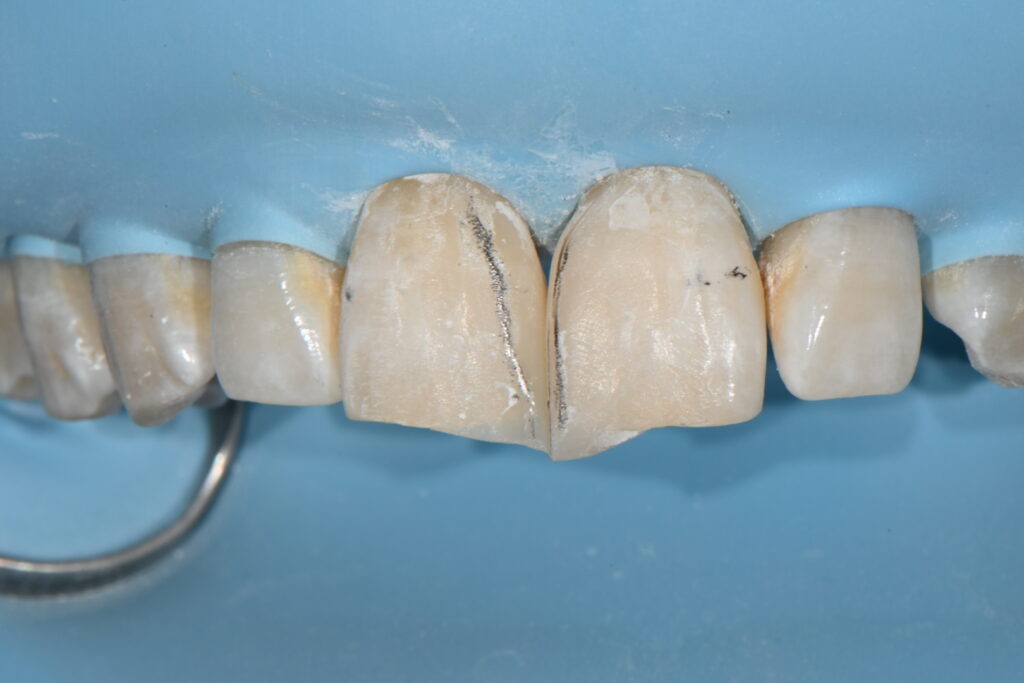

전형적인 잘못된 레진 입니다

1.모양 2.변색 3.파절 모든 레진의 부작용이 일아나고 있네요

일단은 재치료를 위해서는 기존의 레진을 제거해야 합니다

레진을 제거하고 나면 그 공간이 아마도 더 넓어질 것으로 보입니다

보이는것처럼 레진을 제거하고 난 공간입니다

이 공간을 다시 레진으로 재치료를 해보도록 하겠습니다